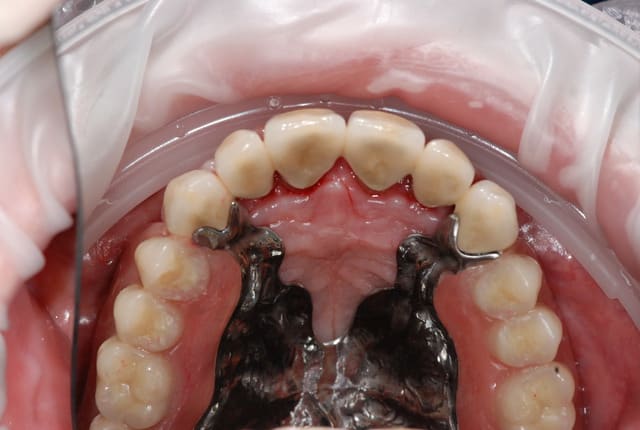

J'ai pris l'habitude depuis une dizaine d'années, de proposer à mes patients des constructions prothétiques avec un ensemble de couronnes antérieurs solidarisées (généralement de canine à canine) associées à un stellite par le biais d'attachement Bredents extra coronaires (cf photos = jours de la pose).

Dommage car c'est un cas très beau et très propre sur le plan prothétique.